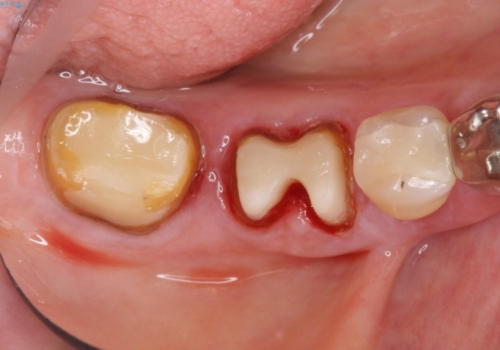

- 歯ぐきからの出血と腫れを主訴に来院された患者様です。

プラークコントロールが非常に悪く、全顎的な歯周病に罹患していました。

「抜歯したくない、インプラントは嫌」という患者様のご希望とご年齢を考慮し、可及的な骨外科処置や根分割術によりできるだけ今ある歯を残す治療方針をたてました。

保存不可能な左上の奥歯2本(左上67)は抜去し、ノンクラスプデンチャーをいれることにしました。